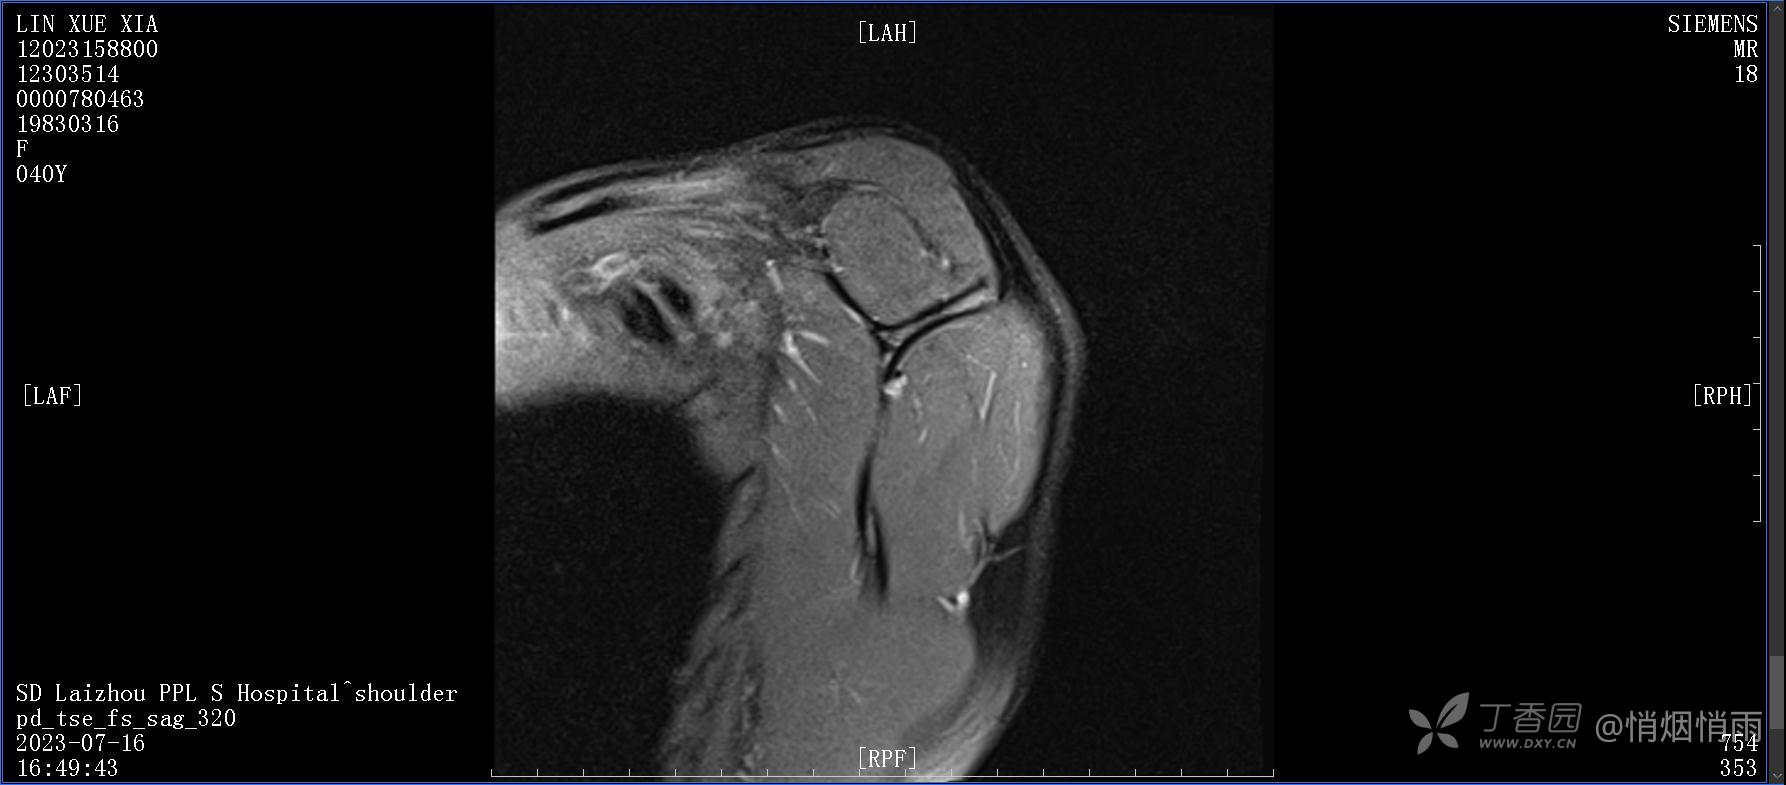

查体:右肩关节局部轻度肿胀,肩胛区压痛明显,痛处不固定,肩关节痛性活动受限,jobe test(+),lift -off test(+),中指、环指感觉较余指减退,余肢端感觉及血运情况可。

目前的诊断,暂时依据辅助检查诊为肩袖损伤,但是患者疼痛的性质和特点,却不是单纯的肩袖损伤所致。考虑过胸廓出口综合征,但是该疾病会出现肩胛区的疼痛吗?(由于考虑到费用的问题,没再进行下一步的检查)带状疱疹会有如此的症状吗?